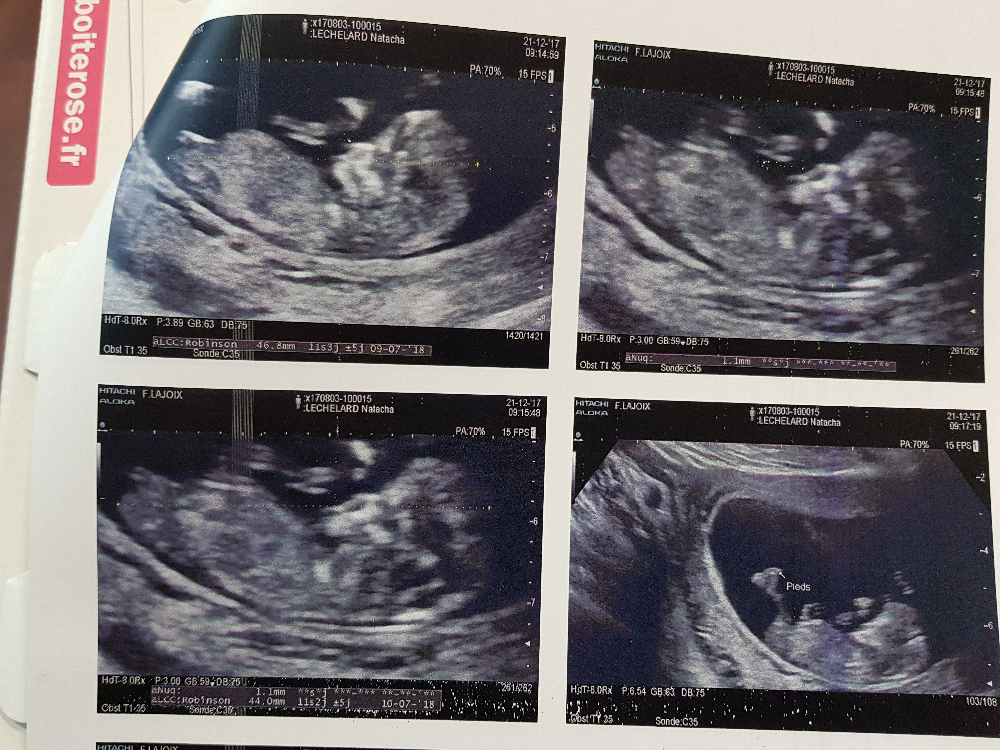

Echographie De 11 Semaine Elle Messure 4 6 Cm Elle Suce Deja Son Pousse C Etait Trop Mimi Et On Na Pu Voir Son Sex J Attend Encore Une Fille Lol 3

Echographie 11 Semaines 2 Jours Notre Histoire Notre Amour Notre Bebe

Echo a 11 semaines et 3 jours Dernier message postéCette échographie permet presque deLa 9e semaine de grossesse À